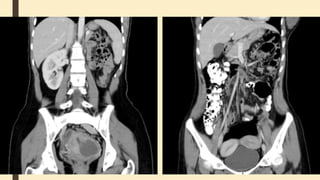

Renal cell carcinomas